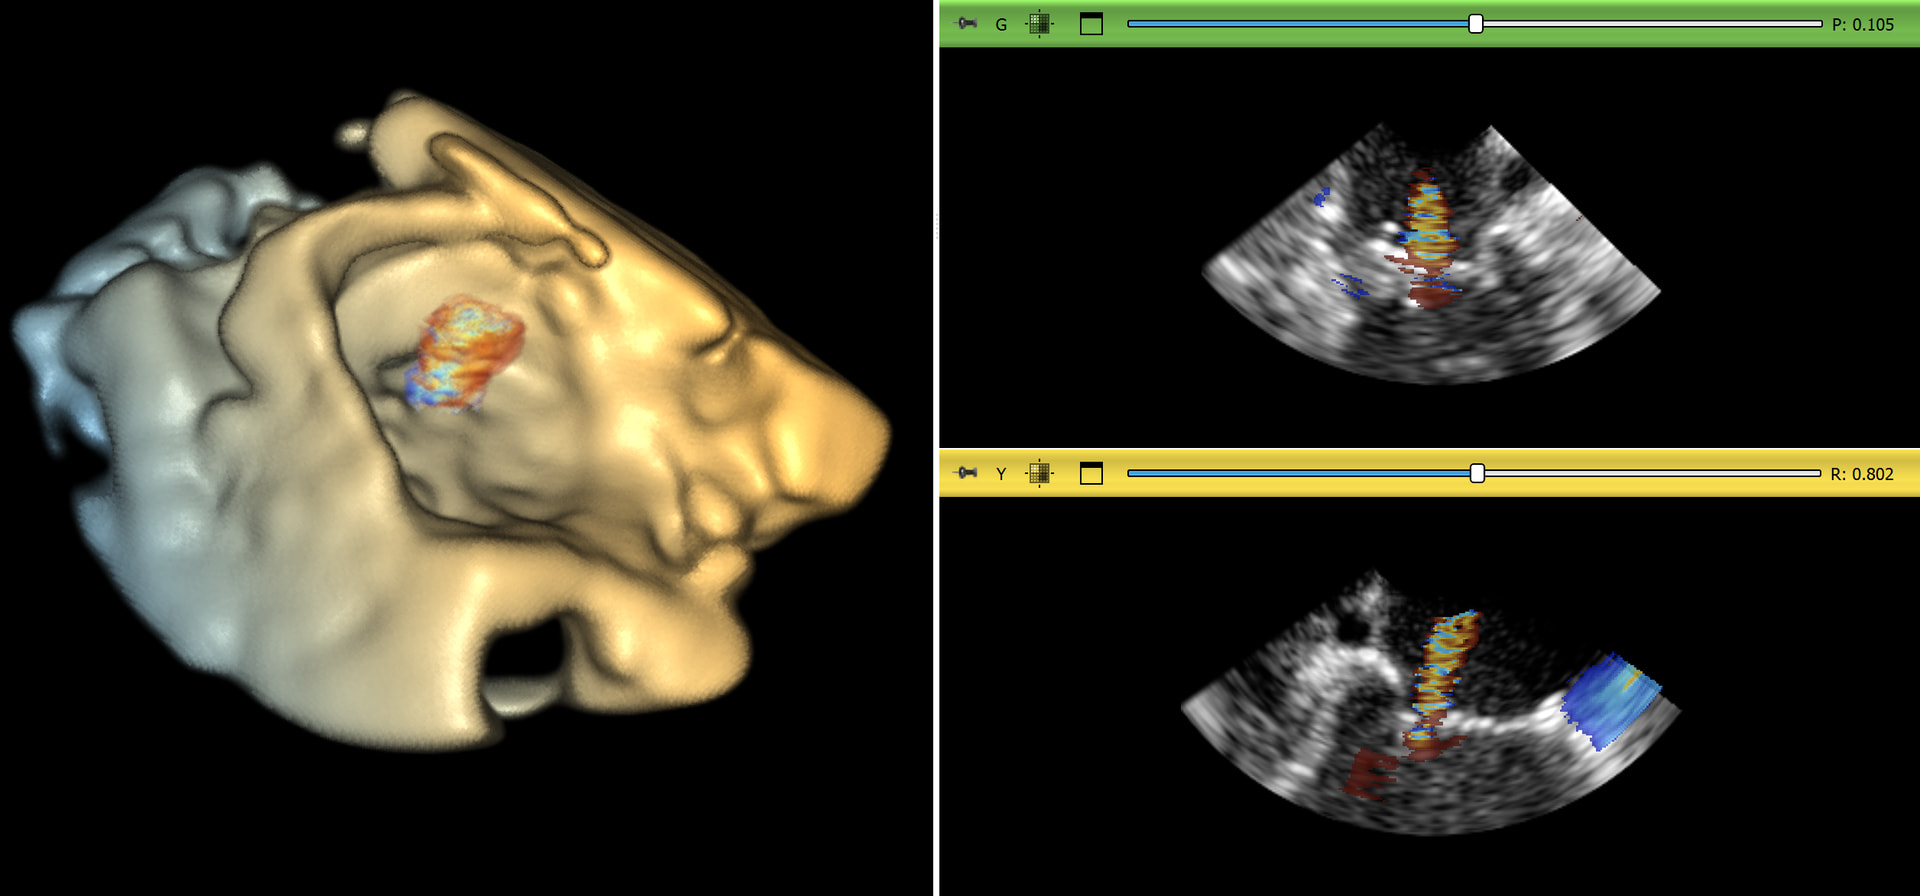

- Color volumetric image (cxyz) - for example cryosection images (such as the visible human data set) or multichannel/multimodal images (such as B-mode + Color Doppler)

Multi-modality image storage

Cardiac ultrasound systems can acquire 3D B-mode ultrasound image time sequences, which were stored as 4D image volumes. Some systems can simultaneously acquire B-mode and Color Doppler (velocity) images. Since the resolution and field of view of these images are very similar, they can be robustly and efficiently displayed in 3D as a multi-component volumetric image. However, previously there was no way of storing a sequence of these fused multi-component volumetric images efficiently in one data file.